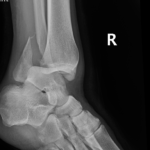

- Ankle Fractures.